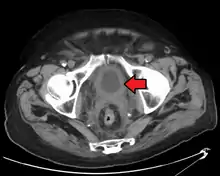

Bladder wall thickening due to cancer

Bladder tumor in FDG PET due to the high physiological FDG-concentration in the bladder, furosemide was supplied together with 200 MBq FDG. The uptake cranial to the lesion is a physiological uptake in the colon.